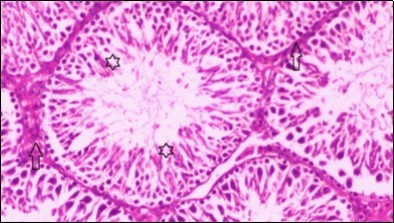

Figure 7.Photomicrogragh of testis section of treated rat with combination of Fenugreek and Glimepiride showing nearly normal appearance of seminiferous tubules with organized spermatogenesis end with large number of spermatozoa (star). Note, Sertoli cells (arrows). (H&E) (40X).

Photomicrogragh of testis section of treated rat with combination of Fenugreek and Glimepiride showing nearly normal appearance of seminiferous tubules with organized spermatogenesis end with large number of spermatozoa (star). Note, Sertoli cells (arrows). (H&E) (40X).

Histological examination of control rats' testis showed normal histological structure of the seminiferous tubules with an increase in the spermatogonia and other spermatocytes compared with the diabetic rats which showed an obvious decrease in the count of germinal cells generally and sloughing of germ cell in the lumen of seminiferous tubules in addition to absence of the mature sperms (Figure 3 and Figure 4). Rats tested of Fenugreek group and those treated with Glimepiride (Figure 5 and Figure 6) presented an increase in the number of spermatogenic cells and mature sperms with few focal necrotic cells. Whereas the combination therapy group showed normal histological structure of the seminiferous tubules with normal spermatogonia, presence of ledying cells and more mature of sperms (Figure 7). STZ reduced testosterone production, suggesting a decrease in the function of both Leydig (testosterone producing cell) and Sertoli (spermatogenesis) cells, which might be caused by a reduction in insulin secretion. These changes are probably due to increased Reactive Oxygen Species (ROS) production by accelerated Advanced Glycation End Products (AGE) formation 31 hexosamine and Protein Kinase C pathway. The administration of Fenugreek seeds to diabetic rats significantly decrease of sperm shape abnormality and improve the sperm count 32. Glimepiride reduced sperm abnormality and increased testis weights and sperm count by its antioxidant action 30. The potential protective efficacy of Fenugreek seed extract when added to Glimepiride was observed on reproductive systems.